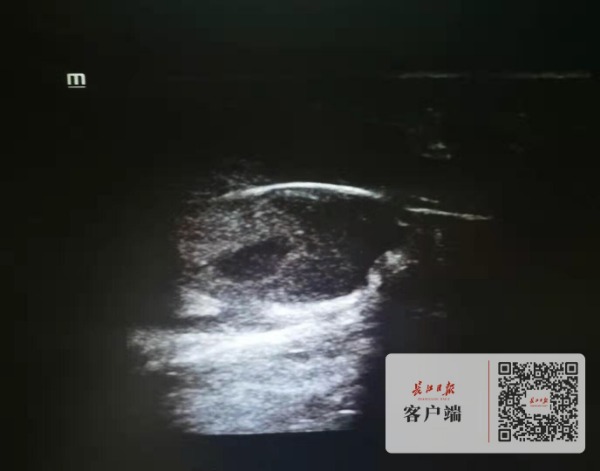

超声检查图像。

医生询问、观察后初步判断,并非单纯的化脓感染性包块。超声检查发现,脓包中有一条粗线一样的强回声影像。医生判断,李先生可能是患上了一种少见的疾病——藏毛窦,并且发生了化脓感染。果然,手术中,医生切开脓包,取出一缕一指长的毛发。